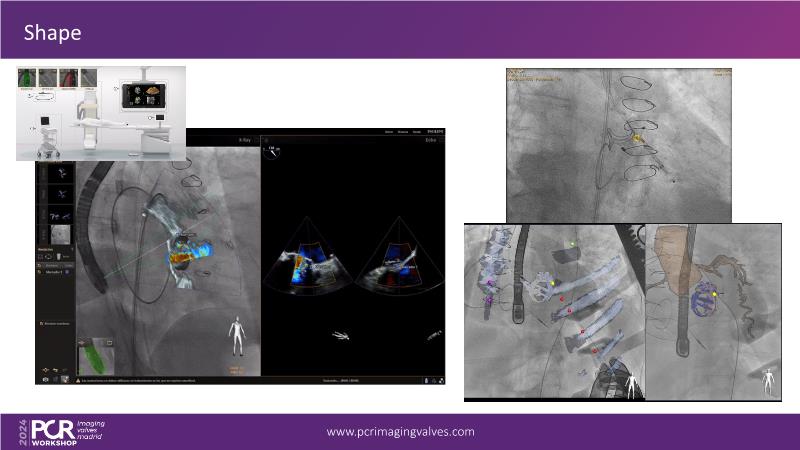

Explore cutting-edge transcatheter valve interventions for mitral and aortic valve disorders, including valve-in-valve procedures and management strategies for paravalvular leakages, and learn about diagnosing and treating mitral annular calcification and transcatheter options in infective endocarditis.

- To get tips and tricks for guidance of transcatheter intervention